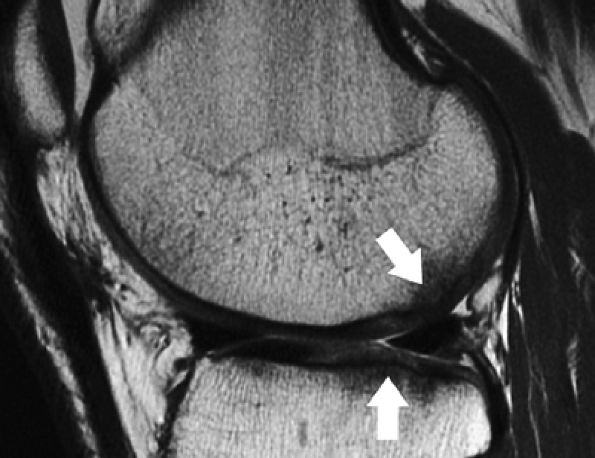

FIGURE 7.10 ● Sagittal (A) and coronal (B) fast spin-echo MR images of the knee in a 24-year-old professional football player. There is hyperintensity in the radial zone, indicating deep surface delamination (arrow), adjacent to the tidemark with no flap formation. There is also associated sclerosis of the subchondral plate. The patient underwent microfracture with a good clinical outcome.